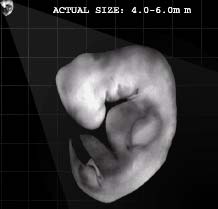

A Korán Allah szava, amelyet Mohammed Prófétának (Allah áldása és békéje Reá) küldött le a Földre Gábriel angyal segítségével. Mohammed Próféta (Allah áldása és békéje Reá) feladata volt, hogy átadja az Iszlám üzenetét az emberiségnek. A Korán így Allah egyik csodája, olvasása közelebb viszi a hívőket Urukhoz, s közbenjáró is lesz a hívőkért az Ítélet napján. A Korán csodás a történetei terén, minden korábbi írásnál sokkal teljesebb, pontosabb leírást ad a Paradicsomról és a Pokolról is, az egész Túlvilágról, a Feltámadás Napjáról, arról, hogy mi történik a halál után. Csodás a törvénykezés terén, az élet valamennyi területére nézve gyakorlati útmutatót is tartalmaz. Egyedülállóságát bizonyítja, hogy amikor még a kalifátus létezett, és egy állam vezetése is az Iszlám törvénykezésnek (Sariának) megfelőlen valósult meg, az az Iszlám fénykora volt, s az embereknek a legjobbat jelentette. Sajnos mára már egyetlen ország kormányzása sem e törvénykezés, azaz az isteni törvények alapján történik. A Korán csodás a tudományok terén is, számos olyan tényt tartalmaz, amelyet az egyes tudományokban csak jóval a kinyilatkoztatása után fedeztek fel. Például a fejlődéstanra vonatkozólag részletesen leírja a magzatfejlődést. Olyan dolgokat is megtalálhatunk benne, amelyeket később a csillagászatban, természettudományok terén fedeztek fel. E felfedezések összhangban vannak a Koránban leírtakkal. (Komáromi, 2005) Jónéhány tudós ezért vált muszlimmá, mert megvilágosodott előttük a Korán csodája a tudomány terén, s minden más tekintetben is.

9 Az ájának ez a része azt jelenti, hogy ha egy muszlim embernek a családtagját megölték és Iszlám bíróság előtt, bírósági per lefolytatása után a gyilkos vétkesnek bizonyult, akkor a legközelebbi hozzátartozó a gyilkos halálbüntetését kérheti. Ettől a jogától azonban el is állhat. Ez kizárólag Iszlám államban történhet meg és csak teljes bizonyosságot nyert gyilkosság esetén. Allah azonban azt is mondja a Koránban, hogy jobb ha a hozzátartozó illetve a család megbocsát inkább a gyilkosnak és nem kérik a halálbüntetését. Ez a törvény leginkább elrettentésül szolgál, azért hogy minden hívő illetve nem hívő is tudja, hogy az emberölésnek mekkora súlya van és meg se forduljon a fejében egy ilyen tettet elkövetni. Illetve, hogy annak, akinek mégis ilyen szándéka van, azt visszatartsa ez a törvény ettől a tettől. Egy hívő embernek azonban nyilvánvalóan nem lehet soha ilyen szándéka, de még gondolata sem.